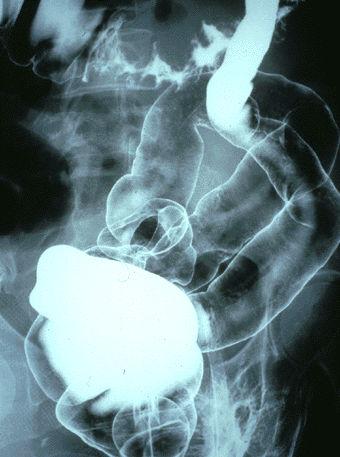

Hemorrhagic colitis caused by Escherichia Coil 0-157 simulating multiple malignant lymphoma.

Inflammatory or ulcerative disease / lesions/Escherichia coli associated colitis

Location

Large intestine(Colon)/Transverse colon

Technique, Method

X-ray